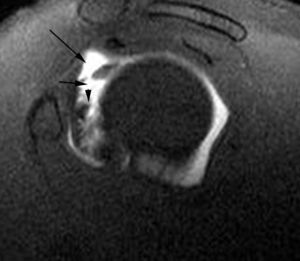

GLAD (gleno labral articular disruption)

El GLAD puede acompañar a cualquiera de las patologías que se discuten en este artículo, afectando al LG. Se trata de una disrupción de un fragmento de cartílago articular junto a la lesión del LG20 (fig. 16).

Fig. 16.--Lesión de GLAD (gleno labral articular disruption). Artrorresonancia axial T1 con supresión grasa donde se puede observar una rotura del labio glenoideo anterior y posterior (flecha). El labio glenoideo anterior está más desplazado. Se ve un fragmento de cartílago articular separado de su posición normal en la cavidad glenoidea y adherido al labio glenoideo anterior (cabezas de flecha).